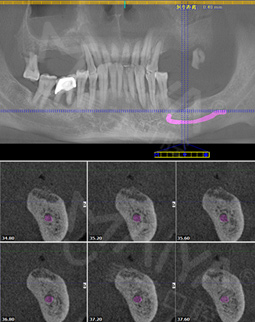

2016年10月 多颗牙缺失,敲定种牙方案

拍摄了CT,牙齿哪个地方有问题,看的很清楚,非常科学。但是口内有牙周病,需要先治疗再进行种牙,而且他们服务特别好,等待的时候还给倒水,安抚我让我感到很亲切,做了口内全口洁牙+喷砂+抛光+上药去除牙结石,是两个护士给洗的牙,一个细节就能提现这个机构好不好,卫生、环境方面都很不错,我也希望可以早点治疗好,做种植牙!

2017年10月 完成种牙,感谢麦芽口腔

一想到中国人的春节,就是一家人热闹的吃个团圆饭,没有一口好牙齿怎么行,所以就迫切的希望早点种上牙齿。郑院长为我定制了“MAC数字化精确微创舒适种植”技术,但是我本身血糖高,考虑到我身体因素,分批次种植,经过了一系列检查后,就开始去手术室种牙,真的一点也不疼,舒适的种牙体验,就像被蚊子“叮”了一下牙就种好了,对于我来说,种牙过程很轻松,全程无痛,种完后也不肿不痛的,术后定期复诊就好了,我当天回去没有什么不适感,而且吃东西也不影响。